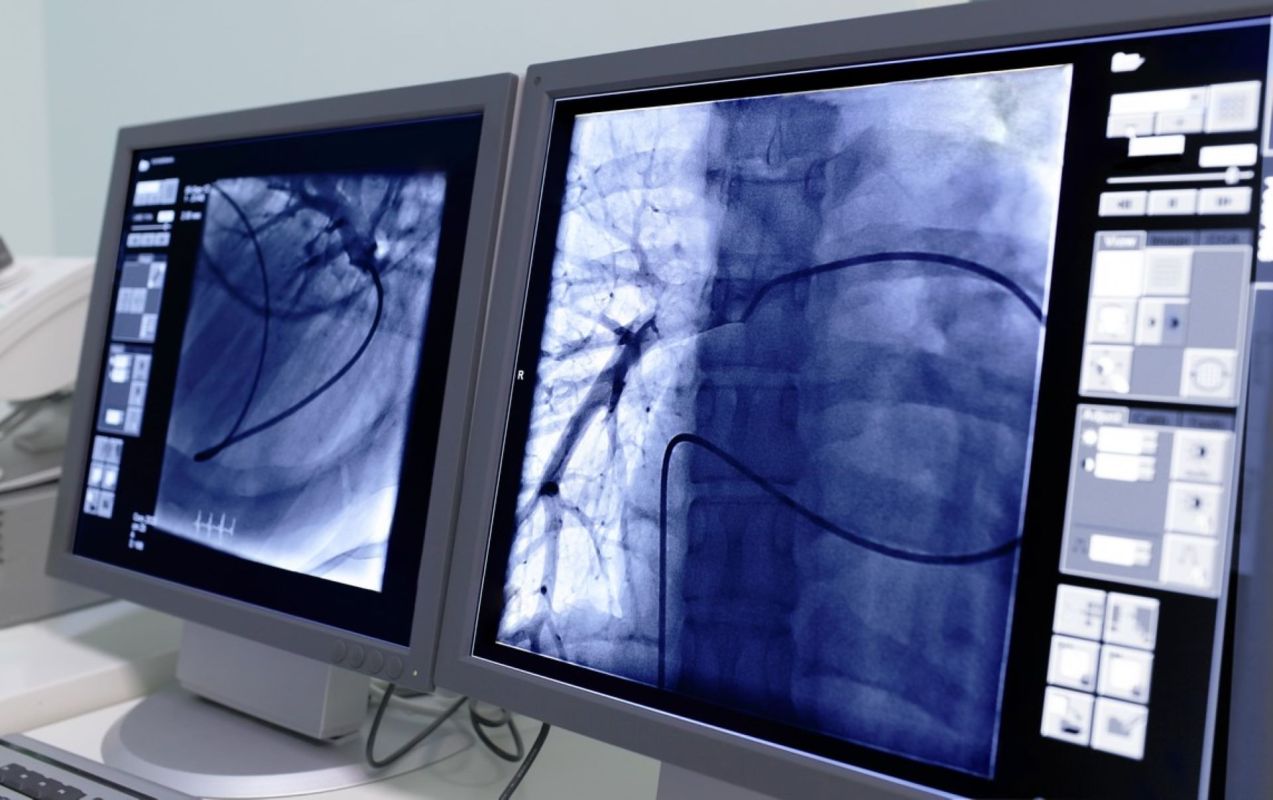

In this limited pilot study, researchers used infrared imaging and scanning electron microscopes to study heart-tissue samples and blood from 15 patients undergoing cardiac surgeries.

In addition to finding microplastics in the heart, the new study indicated that, to a degree, surgery itself exposes patients to these particles. The researchers called for more work in this area and into the effects of microplastics on human health.